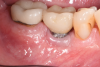

A 56-year-old woman was referred for the treatment of a dental implant at the site of the maxillary right canine, No. 6, which was diagnosed with moderate peri-implantitis subcategory A (Figure 1).19 The implant had been placed 3 years prior and had healed uneventfully, but at a recent maintenance visit purulence and pocket depth of up to 8 mm were noted. The patient's medical history included hypothyroidism, for which she took levothyroxine, and an allergy to sulfa medications. She had a high smile line, and the dental implant was 3 mm wide with an anodized surface.

Fig 1. Pretreatment radiograph of the implant, maxillary right canine site. Bone loss was suggested at the mesial and distal aspects. v

Figure 1